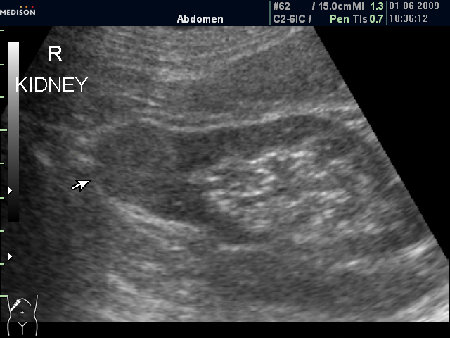

Женщина 72 лет. При УЗИ выявлены два аваскулярные образования: в нижнем полюсе правой почки и у верхнего полюса почки.

Уникальность случая в том, что эти изменения - БЕЗ ДИНАМИКИ с 2005 года.

Опухоль почки?

Опухоль почки и надпочечника.

У пожилых людей опухли чаще всего растут медленно.

Случай из практики - бабушка 73 лет "наблюдала" опухоль почки более 5 лет. После того как было выполнено УЗИ, гордо предъявила старую картинку, где опухоль была миллиметр в миллиметр со свежей картинкой. Я решил, что это доброкачественное образование, например онкоцитома.

Бабушку прооперировали, заключение - почечно-клеточный рак (RCC).

Без допплера явно опухоль почки